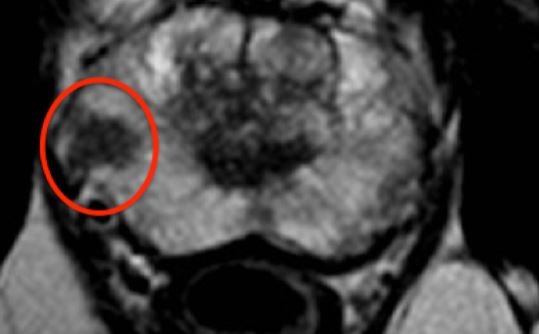

Στο Κέντρο Ελάχιστα Επεμβατικής Ουρολογίας του Ιατρικού Αθηνών έχουμε εφαρμόσει τις πλέον προχωρημένες διαγνωστικές και απαραίτητες εξετάσεις στις περιπτώσεις υποψίας καρκίνου προστάτη. Όταν το PSA ή/και η Δακτυλική εξέταση (ΔΕΠ) θέτουν τέτοιες υπόνοιες, ο ασθενής χρήζει μιας ειδικής μαγνητικής, της Πολυπαραμετικής Μαγνητικής Τομογραφίας Προστάτη. Αυτή αποτελεί τη μοναδική απεικονιστική εξέταση που μπορεί να ανιχνεύσει κλινικά σημαντική εστία καρκίνου προστάτη ακόμα και διαμέτρου λίγων χιλιοστών.

Με οδηγό την πολυπαραμετρική μαγνητική, θα ακολουθήσει η βιοψία προστάτη. Αυτή θα πρέπει να λαμβάνεται όχι μόνο από κάθε περιοχή του προστάτη, αλλά και στοχευμένα από την ύποπτη περιοχή που υποδεικνύει η μαγνητική (σύστημα fusion).